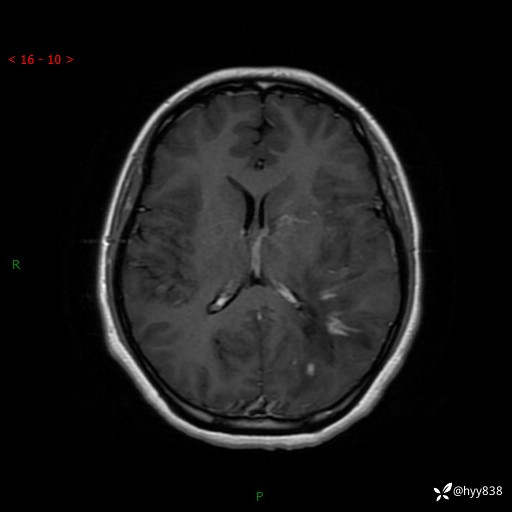

颅脑MRI平扫+增强